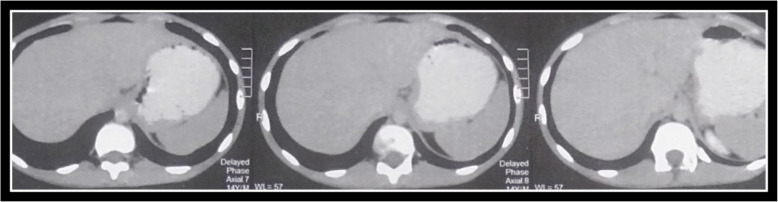

Background: Solid pseudopapillary neoplasms (SPNs) of the pancreas are rare, low-grade malignancies that predominantly affect young females. Their diagnosis is often facilitated by a characteristic histomorphological pattern and immunohistochemical profile. However, diagnostic challenges persist, especially in pediatric and atypical presentations. Recent attention has focused on the diagnostic value of CD99 and LEF1 in distinguishing SPNs from other pancreatic neoplasms.

Results: SPNs exhibited a strong female predilection (F:M ratio ≈ 7:1), with a mean age of 32.5 years. Pediatric cases (n = 4) displayed higher mean expression of CD99 (73.8%) and LEF1 (86.5%) compared to adults. CD99 showed cytoplasmic positivity with paranuclear accentuation in 96.7% of cases, while LEF1 demonstrated nuclear staining in 91.7%. β-catenin nuclear localization was observed in 95% of tumors, reflecting Wnt/β-catenin pathway activation. Cyclin D1 and PR were expressed in 90% and 88.3% of cases, respectively. Co-expression of β-catenin, CD99, LEF1, Cyclin D1, and PR was observed in 73.3% of tumors. CD99 and LEF1 inversely correlated with tumor size and proliferative activity (Ki-67), whereas Cyclin D1 and Ki-67 positively correlated with tumor size and lymphovascular invasion (LVI). Pediatric tumors generally exhibited favorable profiles, with limited evidence of LVI.